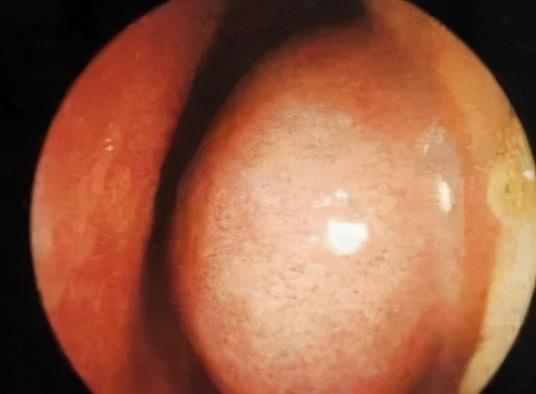

鼻内窥镜下的过敏性鼻炎患者的鼻腔

图片尺寸330x248